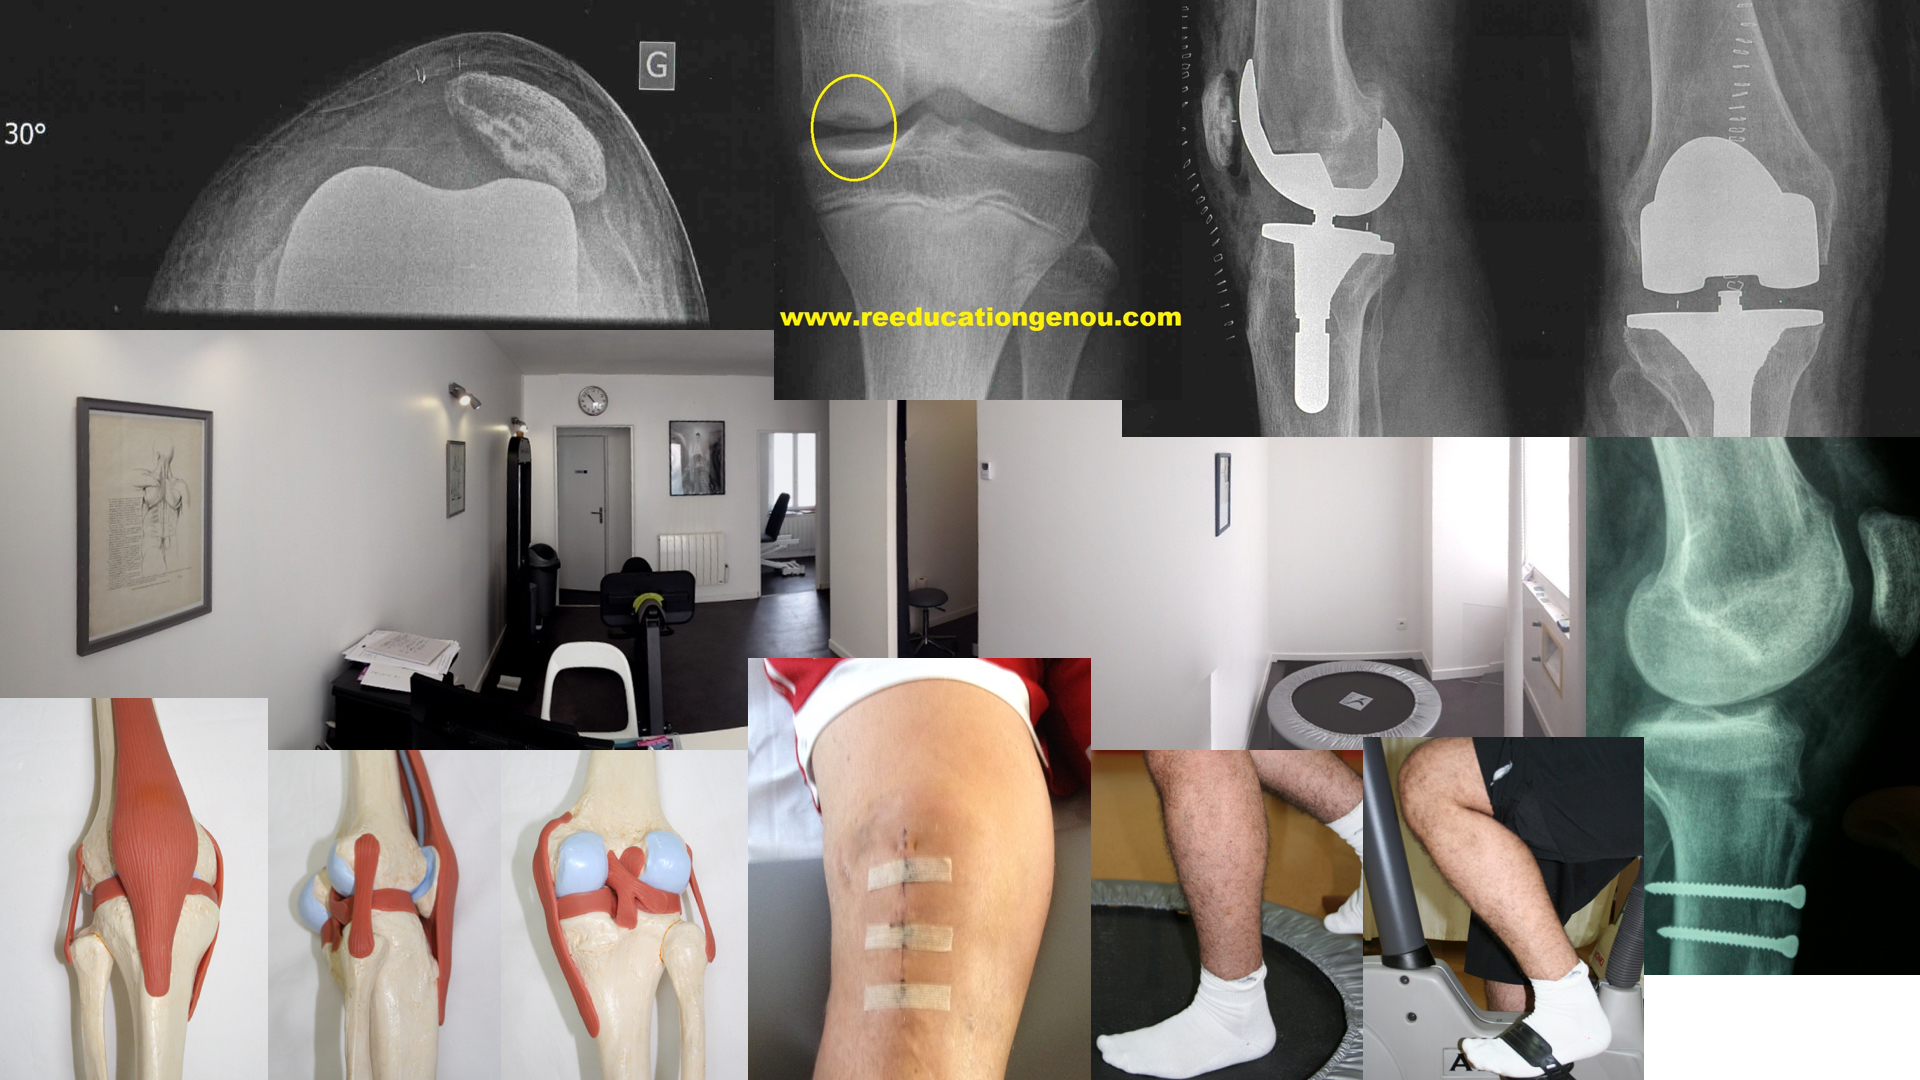

2) Le genou prothétique (ou pré-prothétique)

INTERDIT : le genou sur la béquille !

Les conseils pour le genou prothétique : prothèse totale ou unicompartimentale

• glaçage plus d'une fois par jour les 2 premiers mois, maxi 15 minutes à chaque fois par zone, partout où c'est gonflé, bleu et douloureux. Pour être efficace vous pourrez glacer 15 minutes dessus et 15 dessous...

• la position de repos et de drainage est en extension complète: donc assis le genou tendu quand on ne marche pas. En tous cas tant que le genou est chaud et gonflé.

• Le genou tendu quand on est assis et surtout pas la jambe posée sur la béquille coincée entre le fauteuil et le sol (les sexagenaires en pleine faute dans cette position" ils " le font tous!!! ). Voir la photo ci dessus !!! La flexion est tout de même autorisée et sera recherchée par votre kiné alors il faut alterner tendu -pour le repos le drainage et l'extension- et en flexion pour le gain d'amplitude et la facilité de plier.

• il faut savoir qu'un genou qui a souffert longtemps avant la pose d'une prothèse se "souvient" des douleurs précédentes, la réaxation du membre inférieur et la mise en tension ligamentaire qui va avec peut générer des douleurs à court terme... Le gonflement qui persiste n'est pas toujours un excès de rééducation pour les causes précitées.

• les étirements des mollets sont appréciés et conseillés car ils soulagent les contractures du fait des douleurs d'arthrose et ils redonnent l'extension qui est "consommée" par les mêmes douleurs.

lien vers la page prothèses